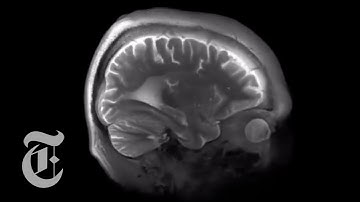

Mapping the Brain